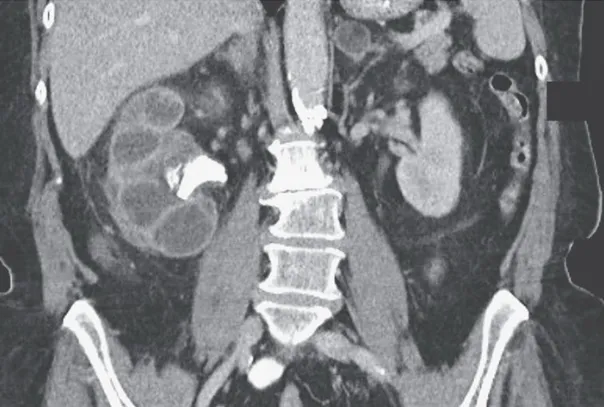

Uma causa incomum de hematúria glomerular intermitente!

Hematúria pós infecção, caso clínicos para auxiliar no entendimento de causas glomerulares comuns e raras...